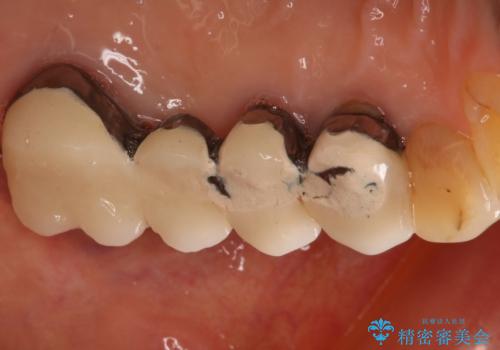

- 数十年前、アメリカで行った治療部位のやり直しを希望されてご来院。

ツギハギの修復が行われてきた被せ物は、縁が合っておらず隙間があり見た目も悪くなってしまっていました。